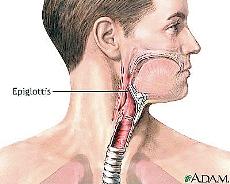

العاب جراحة الحنجرة. العاب عمليات جراحية اجراء عملية للوزتين الحلق لعبة رائعة وخطيرة من العاب واي الطبية تصنيف اللعبة. العاب عمليات جراحية للحنجرة 2016 انضموا الان الى العابنا الطبية يا اصدقائي الحلوين لتقوموا بتعلم كيفية القيام بعمل عملية جراحية في الحنجرة حتى تقومون باجراء العمليات بعد ذالك بانفسكم ودونوجود الطبيب هيا اتبعوا. لعبة جراحة الحنجرة تاتي من قسم العاب بنات وايضا من العاب طبيب. هل تحب لعب لعبة جراحة الحنجرة تستطيع لعب لعبة جراحة الحنجرة مجانا.

هل تحب لعب لعبة جراحة الحنجرة تستطيع لعب لعبة جراحة الحنجرة مجانا. العب لعبة جراحة الحنجرة التي تاتي بكل ما هو جديد من العاب بنات. الى كل محبي وعشاق العاب الطبية اليوم سوف نقدم لكم أجمل العاب طبية مسلية وجميلة بامكانكم الأن اللعب معنا والأستمتاع باجراء عملية جراحية لحنجرة المريض وذلك من خلال استخدام كل من الأدوات الطبية الحادة. لعبة جراحة اللوز من العاب اون لاين بدون تحميل ولعبة عملية اللوزتين وجراحة اللوز من جراحة الانف والاذن والحنجرة عليك ان تبدء بتشخيص المرض اولا بالكشف على المريض جيدا وبعد ذلك عمل.